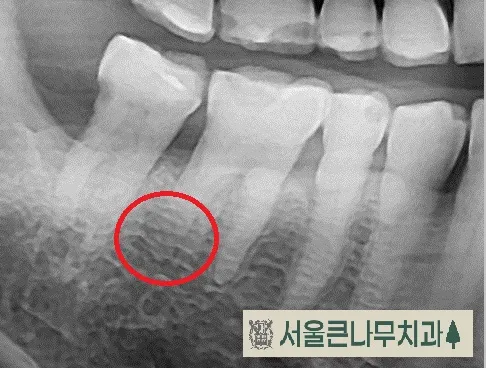

원인 모를 통증으로 내원한 30대 환자분입니다. 진통제를 아무리 먹어도 통증은 지속되었고 극심한 고통으로 잠을 못 이룰 만큼 힘들어하셨습니다.

통증이 있는 치아에는 기존에 때웠던 레진 수복물이 있었고 겉보기에는 문제가 없어 보였지만,

자세한 진단을 위해 CBCT 촬영을 해본 결과, 동그라미 친 부위에 뿌리끝 염증이 발견되었습니다.

이전에 치료했던 레진 수복물이 치수에 가까워 신경에 영향을 주었을 것이라고 판단하고 신경치료에 들어갔습니다.

치아 안쪽을 열어본 결과 신경이 괴사되어 있었고 신경치료 후 환자분의 통증도 거짓말처럼 사라졌습니다.